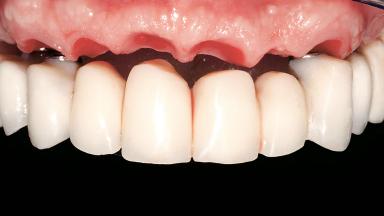

Immediate Loading of Six Implants in the Maxilla and Final Restoration with a Full-Arch CAD/CAM Zirconia FDP

A 63-year-old male patient was referred for a consultation and treatment of partial edentulism in the maxilla. The patient presented with residual anterior teeth and declined a partial removable prosthesis. He reported that the maxillary posterior teeth had been extracted due to mobility and periodontal disease two months before the consultation. The patient’s chief complaint was that his residual maxillary teeth were mobile and that he was unable to chew. The patient’s desire was a stable and comfortable fixed maxillary rehabilitation. The patient was a light smoker (fewer than 10 cigarettes/ day), and his medical history was without significant findings. He was not on any regular medication at the time of consultation. The extraoral examination revealed a normal physiognomy with a correct distribution of the facial thirds. The patient presented a low lip line, and the transition line between teeth and soft tissues was not exposed during a forced smile.

Prosthesis Type FDP

Defining Characteristics Fully edentulous upper jaw to be rehabilitated with an implant-borne fixed dental prosthesis